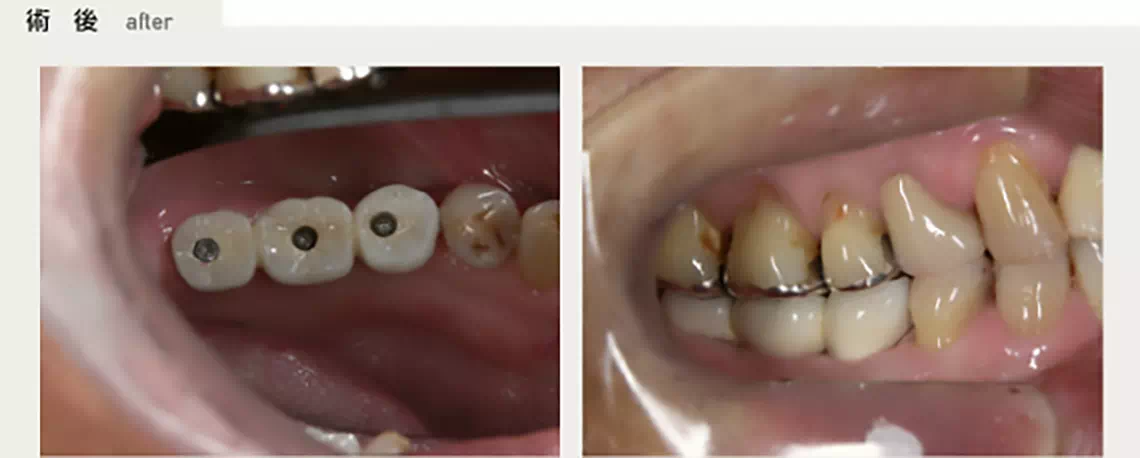

上の両側に部分的に歯が無い方 50代 女性

上の両側に部分的に欠損があり、着脱式の入れ歯を入れていましたが、上顎に右から左へ渡るバーがあり、発音しづらく、お困りでした。入れ歯の煩わしさから解放されたいとのことでインプラント治療を行いました。